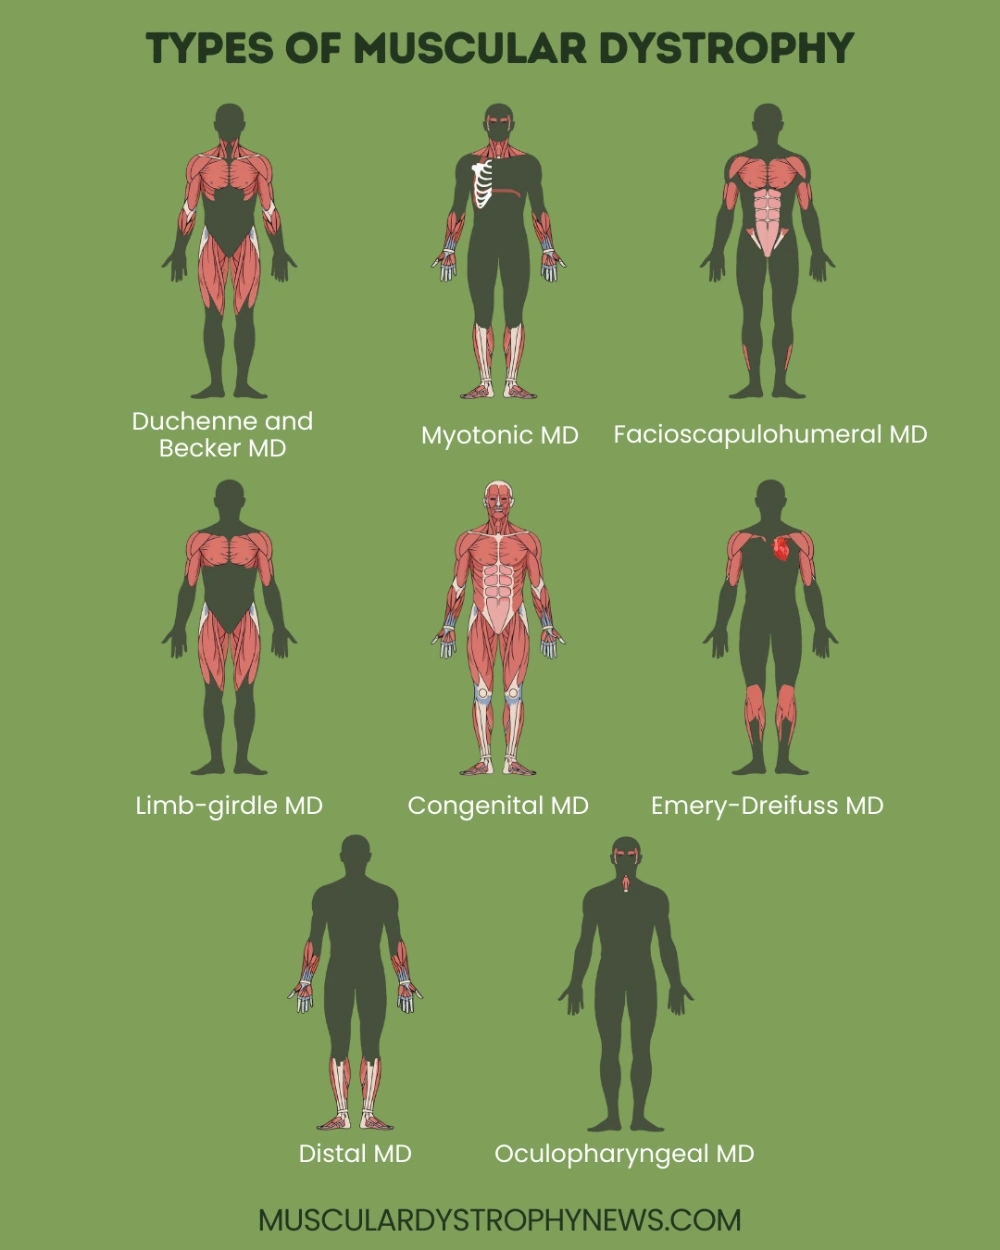

- دیستروفی عضلانی دوشن شدیدترین و شایعترین نوع این بیماری است که تقریباً ۱ از هر ۳۵۰۰ پسر را تحت تأثیر قرار میدهد. این نوع به دلیل جهش در ژن دیستروفین روی کروموزوم X ایجاد میشود که منجر به عدم تولید کامل این پروتئین حیاتی میشود. علائم معمولاً در سنین ۲ تا ۶ سالگی شروع میشود و پیشرفت سریعی دارد. اکثر کودکان مبتلا تا سن ۱۲ سالگی توانایی راه رفتن را از دست میدهند و به ویلچر محدود میشوند. نارسایی تنفسی و قلبی در اواخر نوجوانی یا اوایل بزرگسالی رخ میدهد و متأسفانه امید به زندگی معمولاً به اواخر دهه دوم یا اوایل دهه سوم زندگی محدود میشود.

- دیستروفی عضلانی بکر نسخه خفیفتر دوشن است که همچنان به دلیل جهش در ژن دیستروفین ایجاد میشود، اما در این حالت پروتئین به صورت جزئی تولید میشود نه کاملاً غایب. علائم معمولاً در اواخر کودکی یا نوجوانی شروع میشود و پیشرفت آهستهتری نسبت به دوشن دارد. بسیاری از بیماران تا دهه چهارم یا پنجم زندگی میتوانند راه بروند. عمر بیماران مبتلا به بکر معمولاً طولانیتر از دوشن است و میتوانند تا میانسالی یا حتی بیشتر زنده بمانند، اگرچه مشکلات قلبی و تنفسی در مراحل بعدی زندگی شایع است.

- دیستروفی عضلانی نوع فاسیواسکاپولوهومرال سومین نوع شایع است و هم مردان و هم زنان را تحت تأثیر قرار میدهد. این نوع معمولاً در نوجوانی یا اوایل بزرگسالی شروع میشود و ابتدا عضلات صورت، شانهها و بازوها را درگیر میکند. یکی از نشانههای مشخص این نوع، عدم توانایی در بستن کامل پلکها هنگام خواب و ضعف در لبخند زدن است. پیشرفت بیماری معمولاً کند و متغیر است و برخی افراد ممکن است تنها علائم خفیفی داشته باشند در حالی که دیگران دچار ناتوانی شدید میشوند. امید به زندگی معمولاً طبیعی است مگر اینکه عضلات تنفسی یا قلب به شدت درگیر شوند.

- دیستروفی عضلانی میوتونیک شایعترین شکل در بزرگسالان است و با میوتونی یا سفتی عضلانی مشخص میشود. در این حالت، عضلات پس از انقباض نمیتوانند به سرعت شل شوند، به طوری که بیمار ممکن است پس از مشت کردن دست، نتواند به سرعت آن را باز کند. این نوع دو شکل دارد: نوع ۱ که شدیدتر است و نوع ۲ که خفیفتر است. علاوه بر ضعف عضلانی، بیماران ممکن است مشکلات قلبی، آب مروارید، اختلالات هورمونی و مشکلات شناختی را تجربه کنند. علائم میتواند در هر سنی از کودکی تا بزرگسالی شروع شود.

- دیستروفی عضلانی اندام-کمربندی گروهی از اختلالات ارثی است که عضلات لگن و شانهها را درگیر میکند. این نوع شامل زیرگروههای متعددی است که هر کدام به دلیل جهش در ژنهای مختلف ایجاد میشوند. سن شروع و شدت علائم بسیار متغیر است و میتواند از کودکی تا بزرگسالی متفاوت باشد. برخی از افراد تنها ضعف خفیف دارند در حالی که دیگران به سرعت پیشرفت میکنند و به ویلچر محدود میشوند. مشکلات قلبی و تنفسی در برخی انواع شایع است.

- دیستروفی عضلانی مادرزادی نوعی نادر است که علائم آن از بدو تولد یا در ماههای اول زندگی ظاهر میشود. نوزادان مبتلا ممکن است شل باشند، رفلکسهای ضعیفی داشته باشند و مشکلات تنفسی و تغذیهای داشته باشند. این نوع شامل چندین زیرگروه است که برخی از آنها با مشکلات شناختی و ساختاری مغز همراه هستند. پیشرفت بیماری و پیشآگهی بسته به نوع خاص بسیار متفاوت است.

- دیستروفی عضلانی دیستال نوع نادری است که ابتدا عضلات دستها، ساعدها، پاها و ساق پاها را درگیر میکند. این نوع معمولاً در اواسط یا اواخر بزرگسالی شروع میشود و پیشرفت کندی دارد. بیماران ممکن است مشکل در دستکاری اشیاء کوچک، راه رفتن یا بالا رفتن از پلهها داشته باشند. امید به زندگی معمولاً طبیعی است زیرا عضلات حیاتی مانند قلب و دیافراگم معمولاً درگیر نمیشوند.

- دیستروفی عضلانی امری-درایفوس نوع نادری وابسته به X است که معمولاً در اواخر کودکی یا اوایل نوجوانی شروع میشود. کنتراکچرهای زودرس در آرنجها، مچ پاها و گردن از ویژگیهای مشخص این نوع است. مشکلات قلبی، به ویژه اختلالات ریتم قلب، شایع و جدی هستند و ممکن است نیاز به نصب ضربانساز باشد. پیشرفت بیماری نسبتاً کند است اما عوارض قلبی میتواند تهدیدکننده حیات باشد.